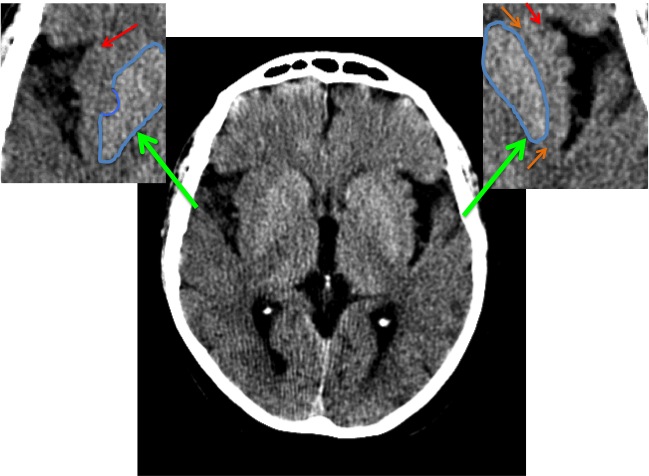

CASO 2:

Paciente con alteraciones del habla y disminución de la fuerza del brazo izquierdo. Ictus previo hace 4 años.

ASPECTS: Territorio M1 + Lenticular derecho = 10 – 2 = 8 puntos.